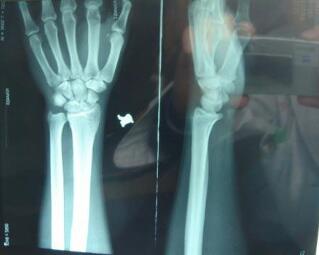

(图:经医托事件后,患者因为失去最佳治疗时期引起关节变形)

来院后,杜爱华主任便开始为赵女士进行一系列全面的检查,4年的误药经历,让赵女士的双手关节肿胀严重,甚至出现变形,手部不仅不可以握拳,伸直也不能,情况比较严重,需要立即开展治疗。在了解了赵女士的病情以及自身状况后,杜爱华主任为她制定了详细的 方案。